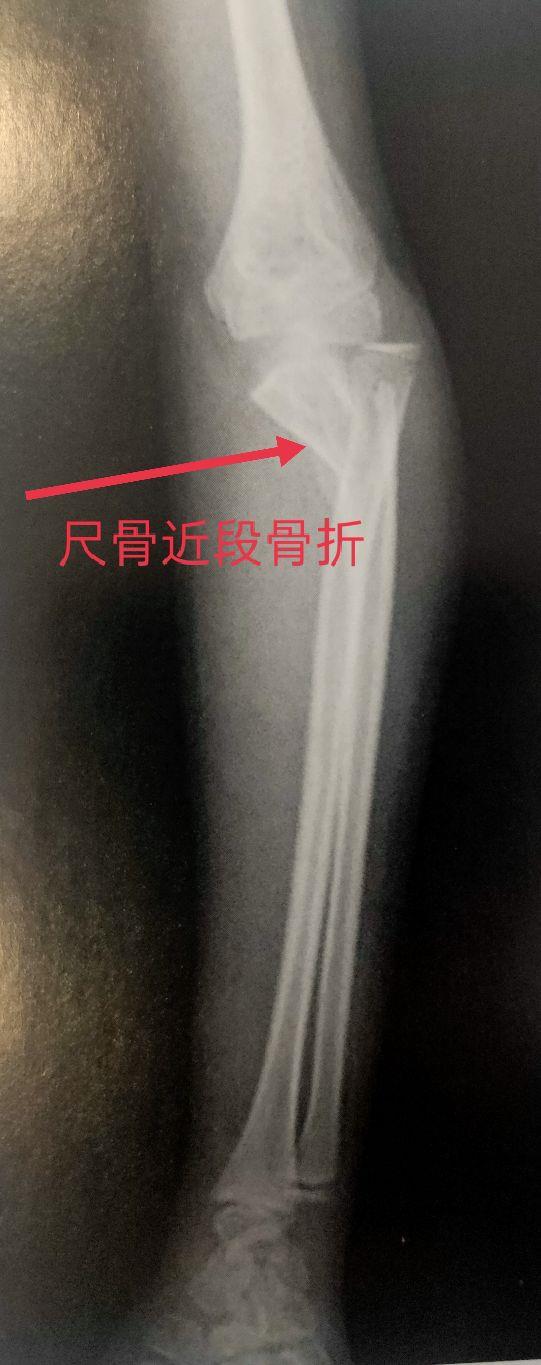

尺骨为前臂的稳定骨,是两根前臂骨中位于内侧且较长的骨,分二端一体。尺骨上端膨大,其上突的鹰嘴呈不整的四方形。它与肱骨滑车下缘相对应,构成肱尺关节。尺骨下端的是尺骨小头和尺骨茎突。尺骨小头与桡骨的尺骨切迹相对应,构成桡尺远侧关节。

四、尺、桡骨骨折X线片

尺骨桡骨骨折以桡骨远端骨折多见。其次是尺骨桡骨双骨折,多发生于青少年。